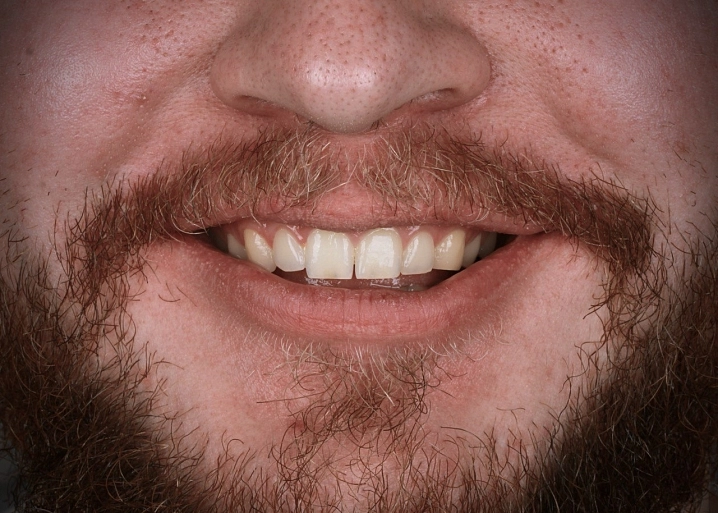

Пациенту изготовлены и установлены 4 винира E-max по технологии CEREC за одно посещение.

Восстановлена эстетика и форма зубов.